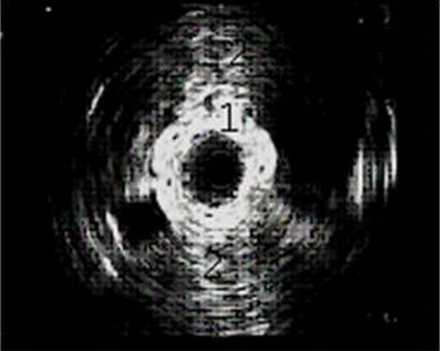

Эндолюминальная эхосонограмма зоны лоханочно-мочеточникового сегмента.

1. Стенка мочеточника.

2. Склероз парауретеральной клетчатки

Состояние парауретеральной клетчатки показывает эндолюминальный датчик, который заводят через мочеточник. Для оценки функциональных возможностей используют фармакоэкографию с мочегонными препаратами.